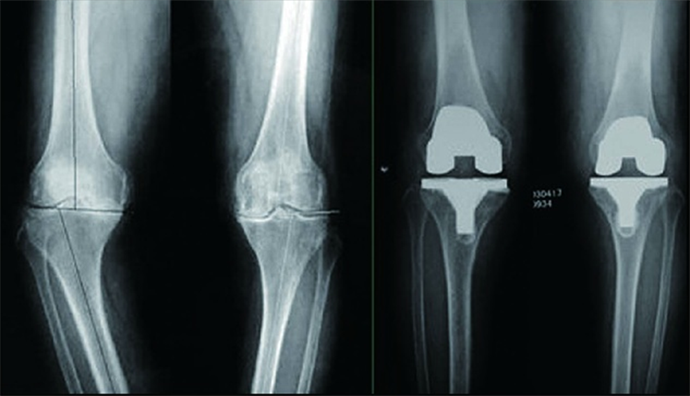

膝關(guān)節(jié)骨性關(guān)節(jié)炎行全膝關(guān)節(jié)置換術(shù)